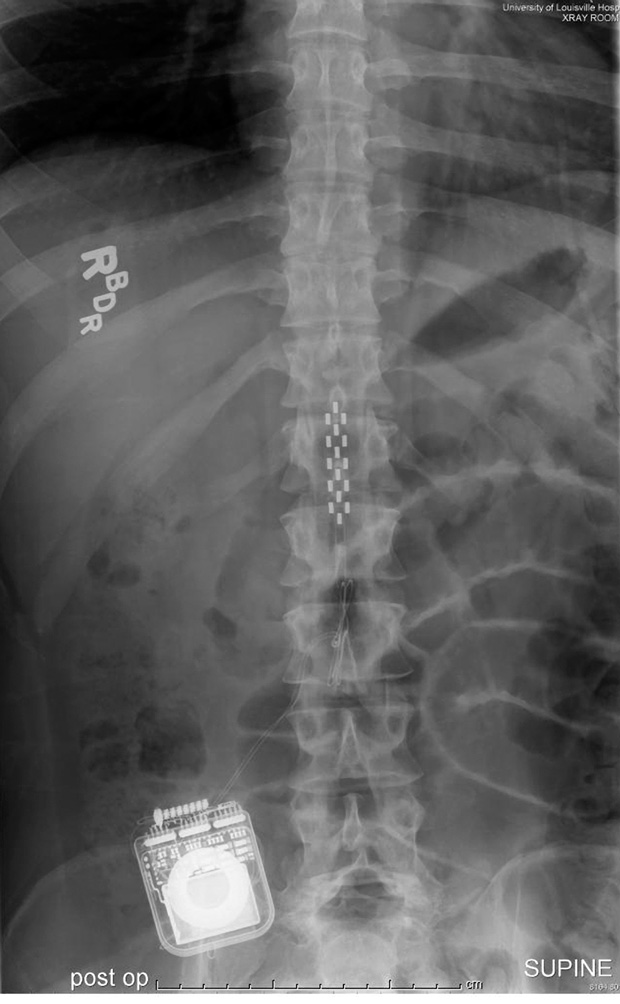

A few months after being discharged from the hospital, in May 2011, Shillcox saw a news report announcing that researchers had for the first time enabled a paralyzed person to stand on his own. Neuroscientist Susan Harkema at the University of Louisville, in Kentucky, used electrical stimulation to “awaken” the man’s lower spinal cord, and on the first day of the experiments he stood up, able to support all of his weight with just some minor assistance to stay balanced. The stimulation also enabled the subject, 23-year-old Rob Summers, to voluntarily move his legs in other ways. Later, he regained some control of his bladder, bowel, and sexual functions, even when the electrodes were turned off.